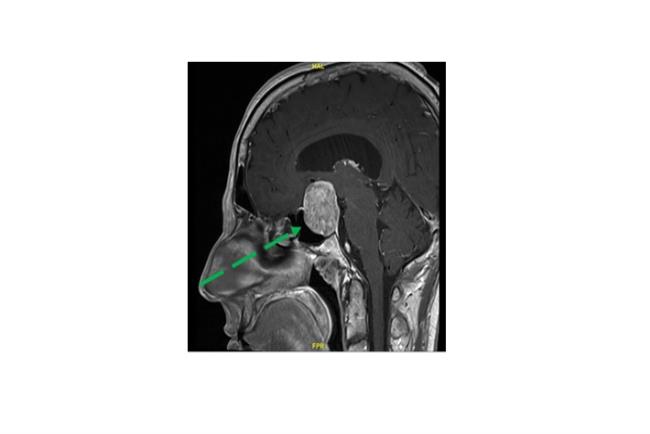

מנינגיומה של בסיס הגולגולת הקידמי (טוברקולום סלה) באישה בת 55 אשר סבלה שנים רבות מכאבי ראש. נותחה בגישה אנדוסקופית (דרך האף) לכריתה מלאה של הגידול

הצלחת הניתוחים האנדוסקופיים של ההיפופיזה הובילה בעשור האחרון ליכולת לבצע ניתוחים לכריתת גידולי בסיס גולגולת מסוגים שונים כגון מנינגיומות, קרניופרינגיומות וכורדומותבגישה אנדוסקופית מתקדמת לבסיס הגולגולת. באמצעות שימוש בגישה זו ניתן למנוע את הצורך בביצוע של הליכים כירורגיים מורכבים המערבים פתיחה נרחבת של הגולגולת ובשל כך גם מצריכים אשפוז ממושך. בדומה לניתוחים אנדוסקופים טרנס ספנוידלים לכריתת גידולים בבלוטת יותרת המוח, ניתוחי המוח המבוצעים בגישה אנדוסקופית מתקדמת לבסיס הגולגולת מאפשרת גישה ישירה לאזור הגידול מבלי לפגום ברקמת המוח. תוצאותיהם של הליכים אלה לרוב טובים יותר, ללא צורך בביצוע חתכים נרחבים בקרקפת או פתיחה נרחבת של הגולגולת , ומצריכים זמן אשפוז קצר יותר.